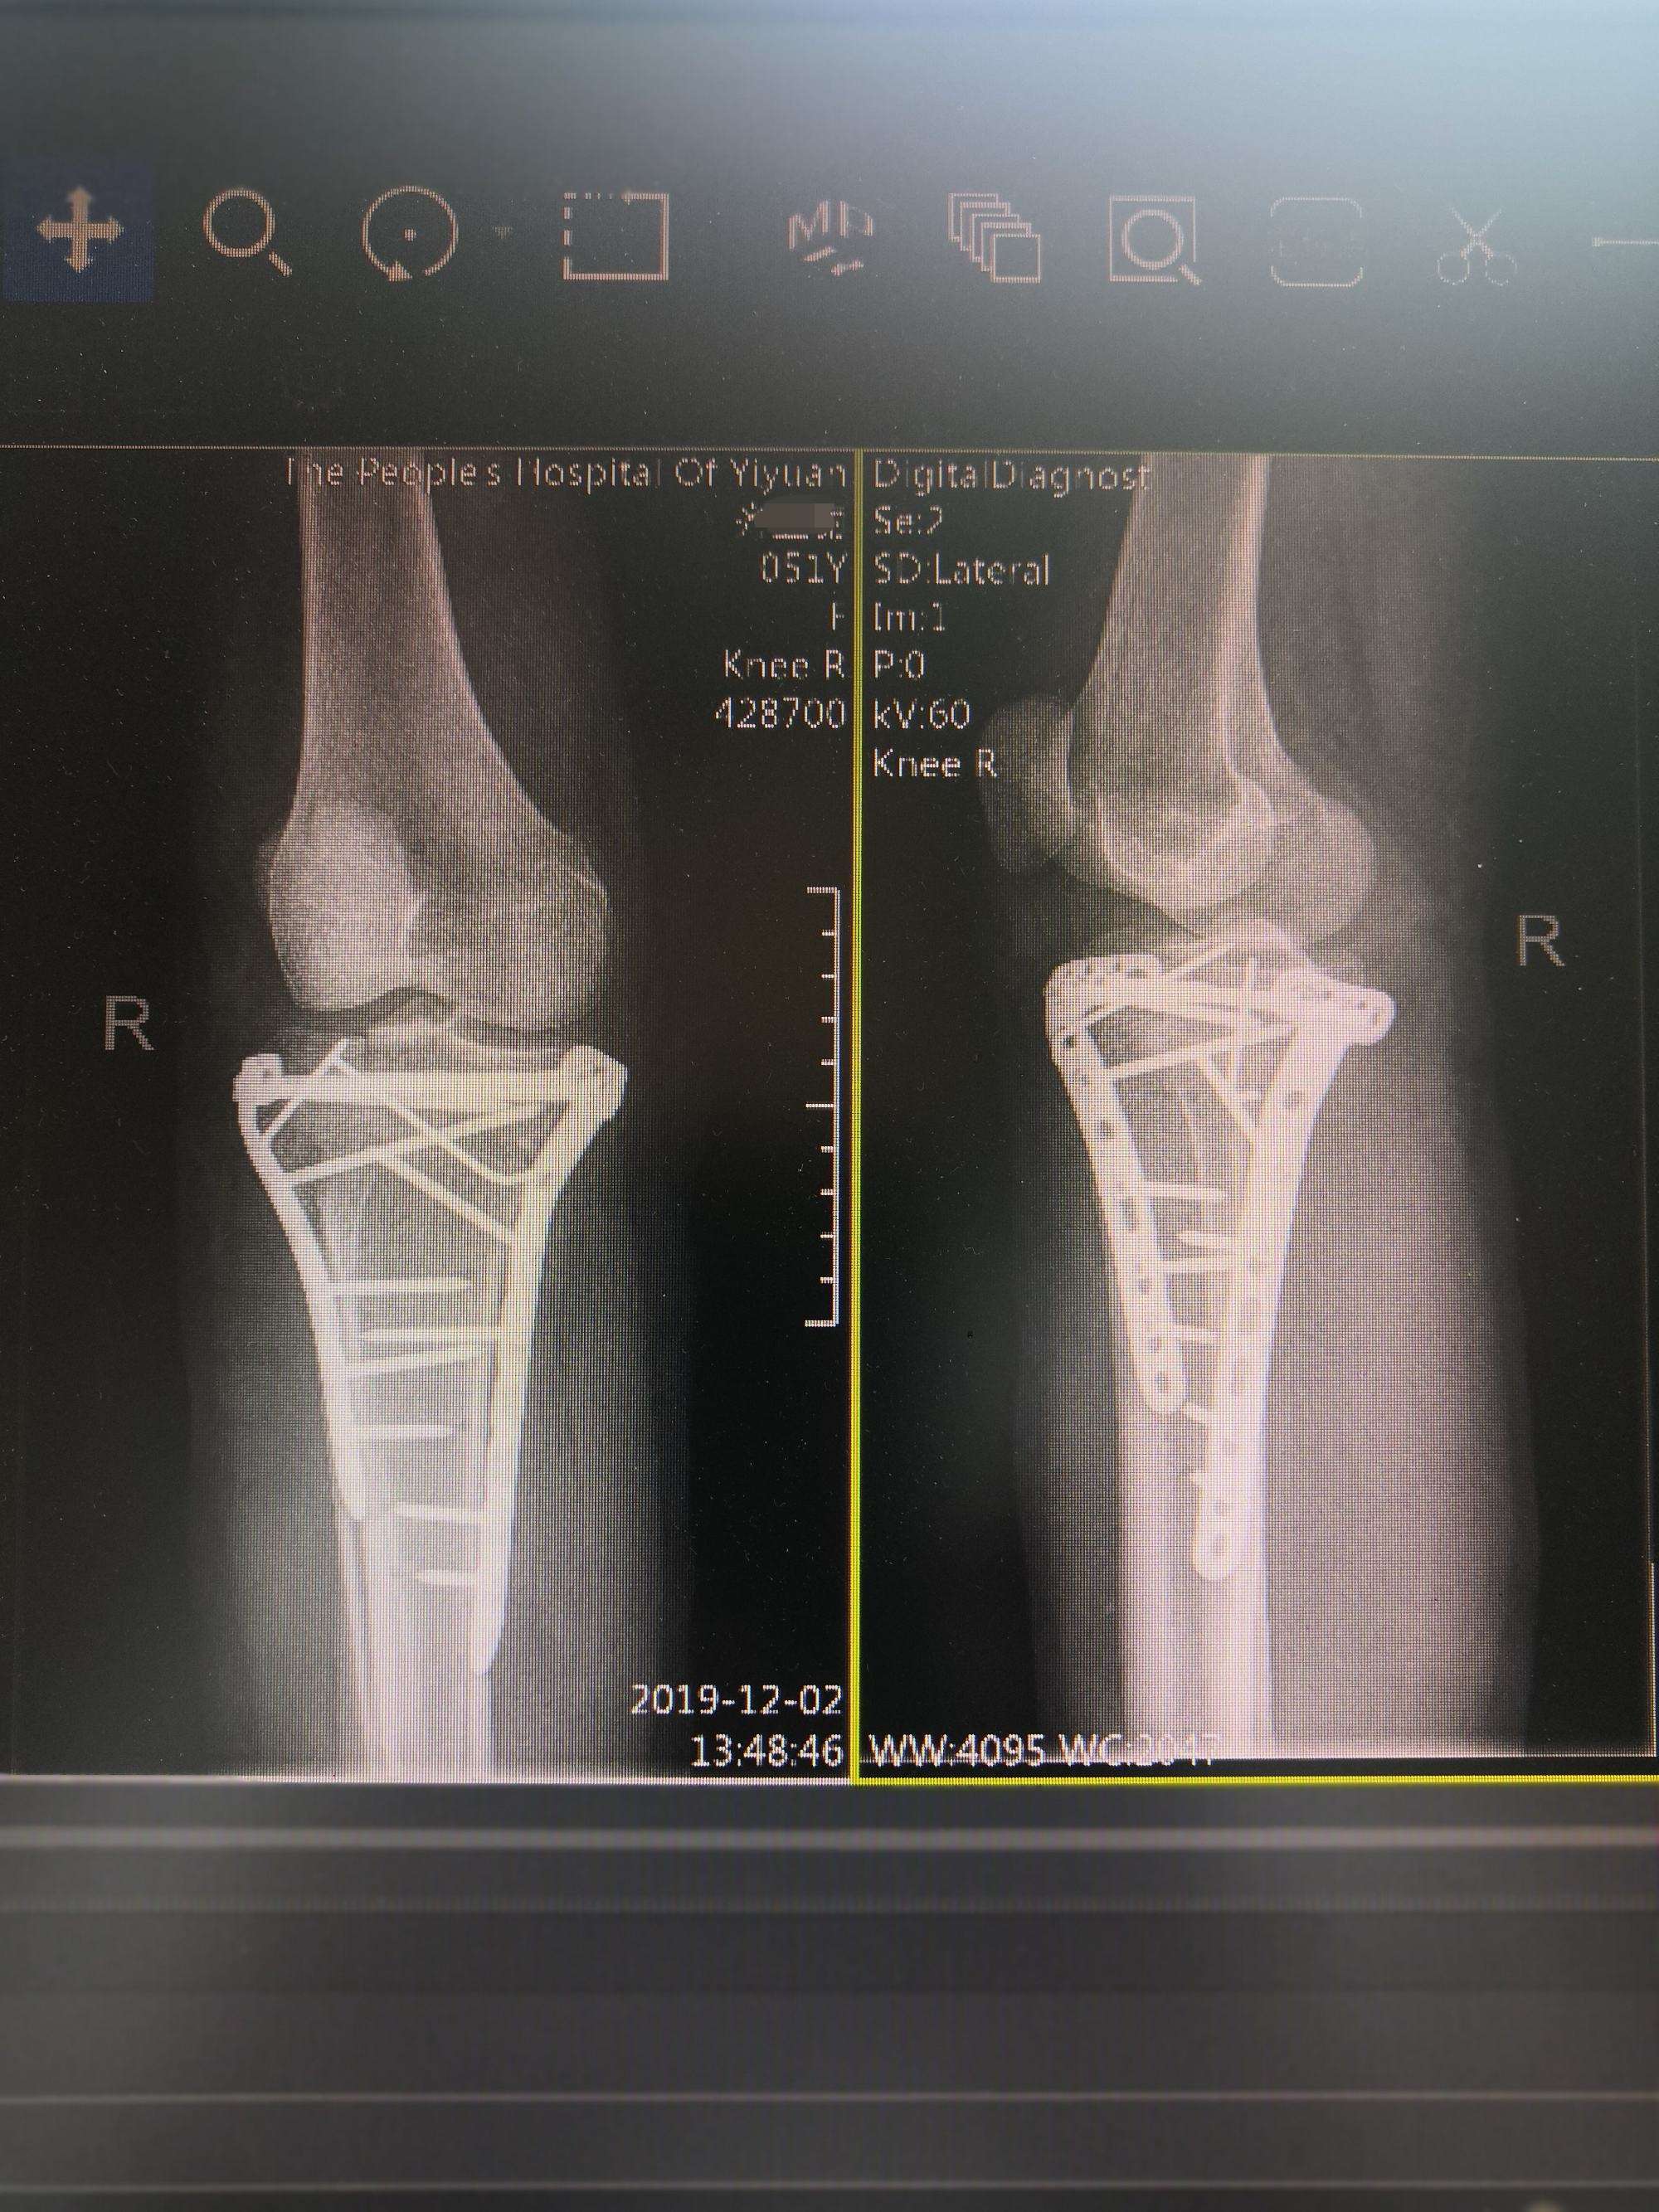

该例患者采取微创理念指导下闭合复位,透视位置满意临时固定,然后仅做皮肤切口,对周围软组织基本不进行剥离,维持软组织张力,降低过多剥离骨膜导致的血运减少,减少暴露时间,降低皮肤坏死及感染率的发证。

同时给予坚强内固定,可以早期进行功能锻炼,最大限度恢复膝关节功能。

进一步复位、植骨内固定

术后复查